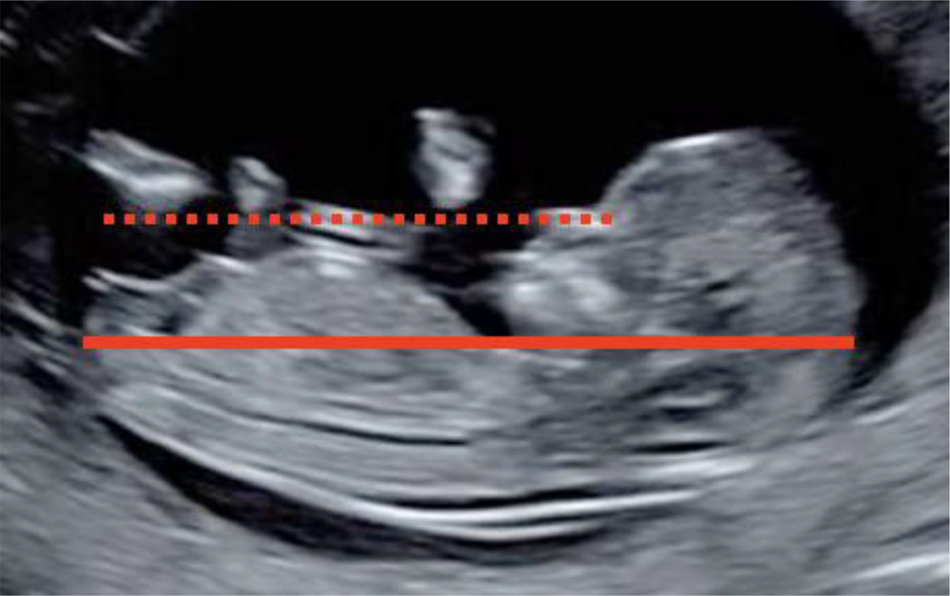

Ensuring strict adherence to international standards is crucial [12], [16], as shown in Figure 1.

CRL measurement standards.

Examination can be transvaginal or transabdominal. CRL between 45 and 84 mm. Midsagittal plane: Sagittal section of the fetus with the head in line with the body. The view must include the echogenic tip of the nose, the nasal bone if present, the diencephalon (do not include the orbit), the insertion of the umbilical cord, the bladder and the genital tubercle. The lower limbs should not be visible. Correct visualization of the cephalic and caudal pole with identification of the crown, the rump and the skin around them. Neutral fetal position, neither flexed (the pocket of amniotic fluid between the lower chin and the thorax must be equal to or greater than the width of the palate); nor extended (Fetal palate angle should be between 30° and 60° with respect to the long axis). Orientation: the plane of CRL should be 0–30° with respect to the horizontal so that the angle between the ultrasound beam and the CRL measurement line is 90°. To ensure that the fetal length is as close as possible to the horizontal, draw a line from the tip of the nose, which should be at the level of or above the abdominal wall with respect to the horizontal. Magnification: the CRL should occupy more than 60% of image space and the entire crown-rump must be seen. Correct caliper placement: place the calipers on the outer border of the skin on the fetal head and rump. Measure the CRL three times and report the mean of three acceptable measurements.